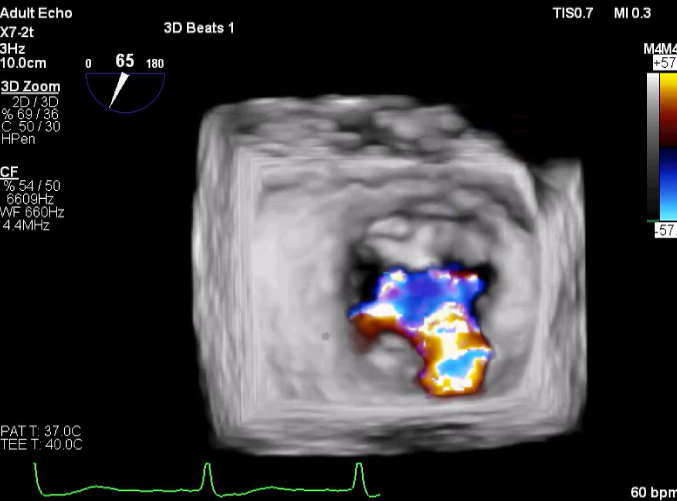

X-plane:下第夹子尝试捕获2区

X-plane:测量前叶长25mm,后叶长14.2mm

X-plane:计算前叶捕获长度8mm,后叶捕获长度7mm

3D-color:残余少量返流